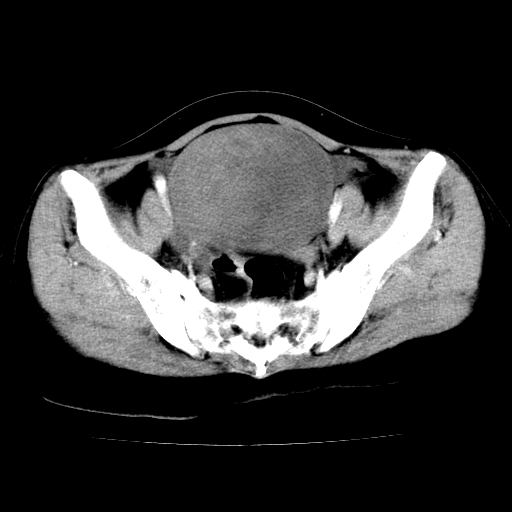

标题: CT24785:女,62岁,发现下腹部肿物半年。 [打印本页]

标题: CT24785:女,62岁,发现下腹部肿物半年。

女,62岁,发现下腹部肿物半年,下腹部不适。

考虑附件粘液性囊腺瘤可能性大。

考虑附件囊腺癌。

考虑卵巢囊腺瘤或囊腺癌可能。